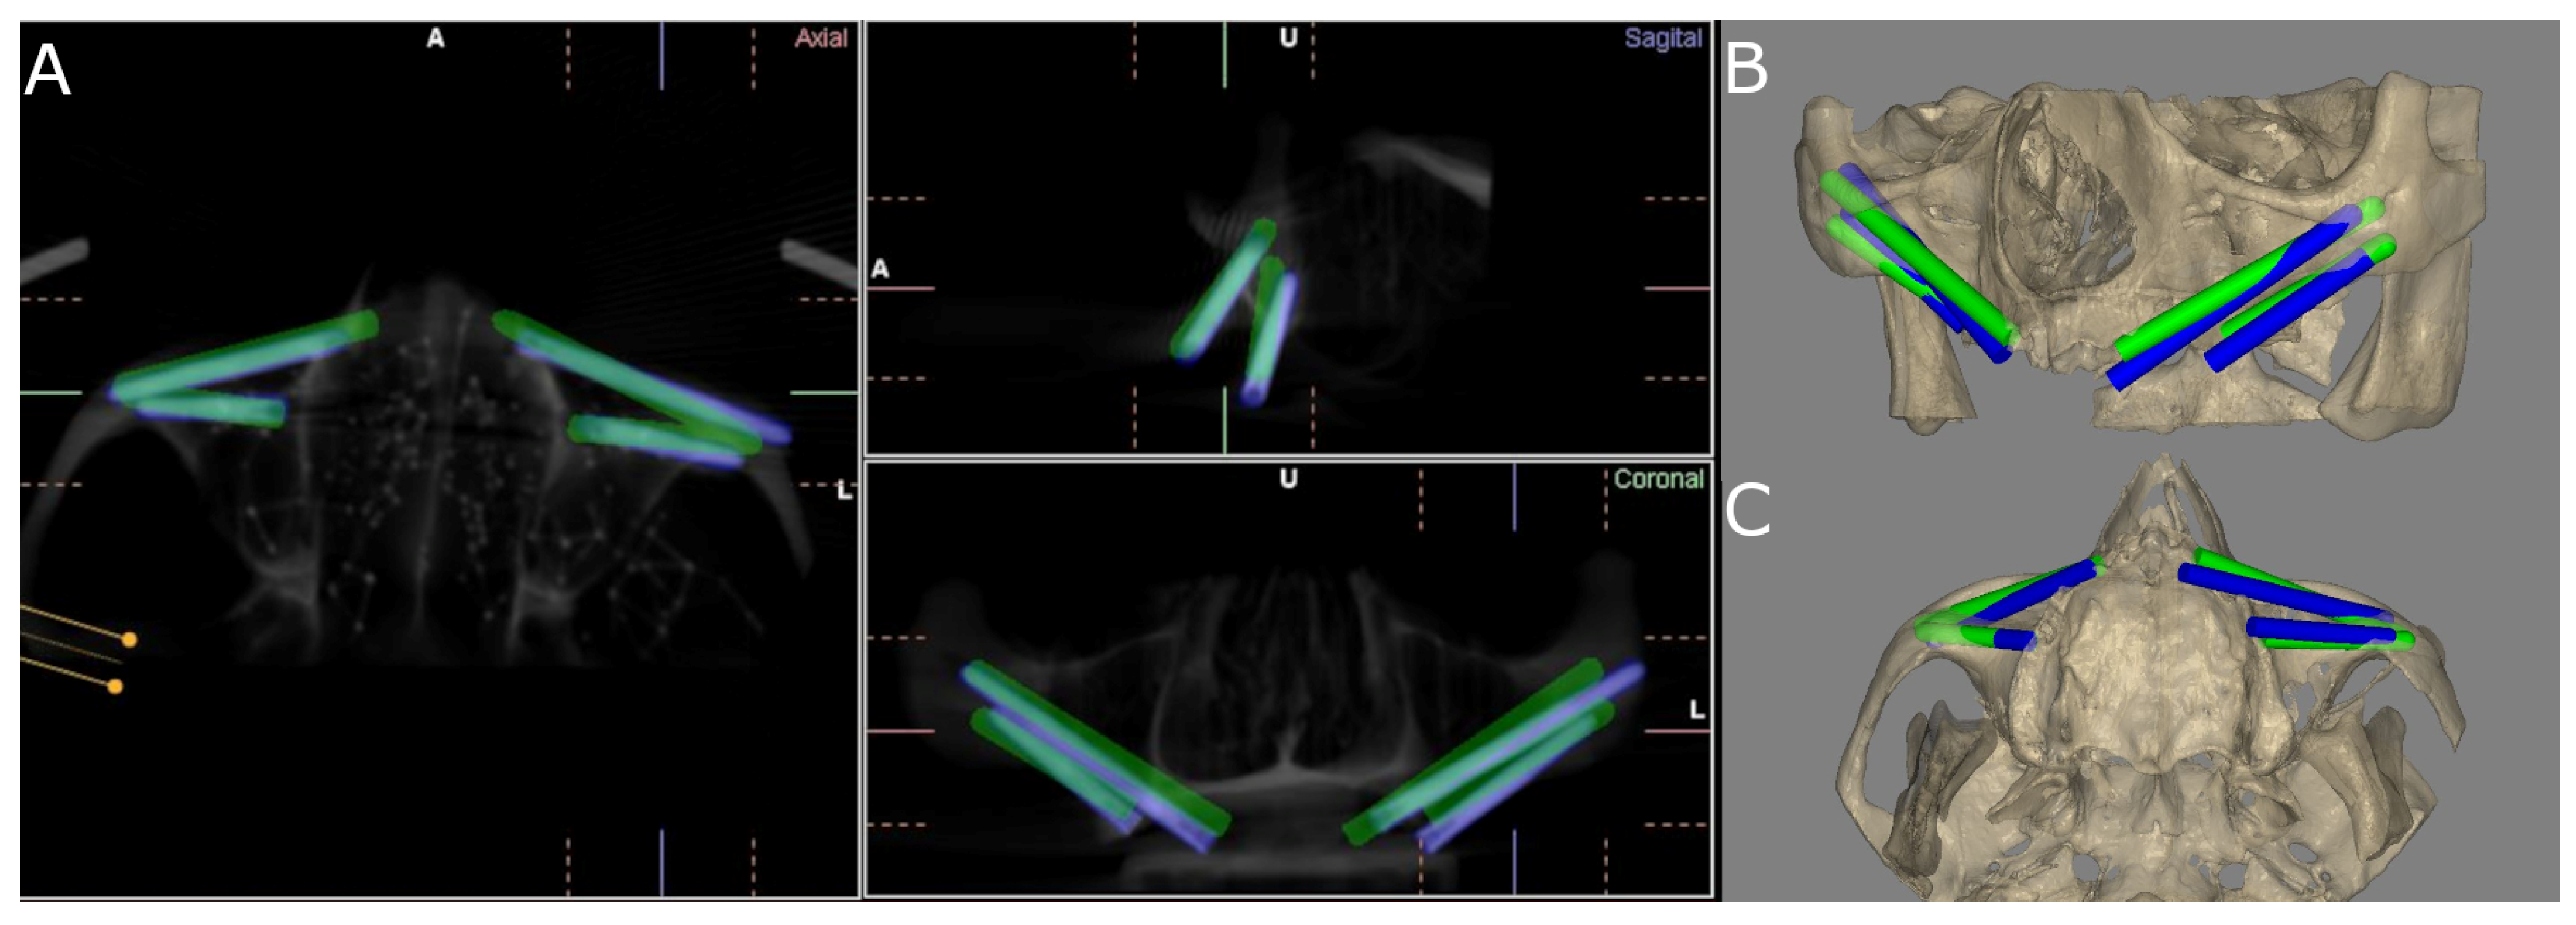

2.2. Experimental Procedure

2.3. Measurement Procedure